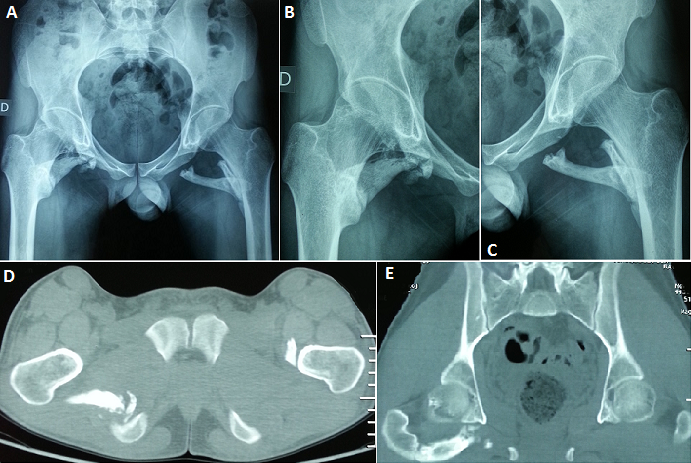

La myosite ossifiante circonscrite est une affection bénigne caractérisée par une prolifération hétérotopique d'os dans les tissus mous. Elle survient généralement chez des adolescents ou de jeunes adultes. De très rares cas ont été décrits chez les enfants. Son étiopathogénie n'est pas claire, il semble toutefois qu'un foyer de nécrose musculaire ou un hématome puissent être à l'origine de la lésion. Les sièges les plus fréquents sont le quadriceps et le biceps brachial. Nous présentons le cas d'un patient âgé de vingt ans, aux antécédents d'hémophilie A, admis dans notre service de Médecine Physique et de Réadaptation Fonctionnelle pour prise en charge d'une limitation de la mobilité des deux hanches. L'histoire remonte à un an où le patient a présenté suite à une chute de sa propre hauteur avec réception sur les hanches une douleur et une tuméfaction à leur niveau. L'évolution était marquée par l'installation d'une limitation de la mobilité des deux hanches responsable d'une gêne fonctionnelle et d'une réduction du périmètre de marche. L'examen clinique objectivait une limitation douloureuse de la mobilité des hanches sans autre signe accompagnateur. Les radiographies standards (A, B,C) et le scanner du bassin (D, E) ont montré une ossification musculaire autour des deux hanches, aspect compatible avec une myosite ossifiante progressive des muscles carrés fémoraux des deux côtés et du jumeau inférieur droit. Une intervention chirurgicale a été proposée mais refusée par le patient. Il a alors bénéficié d'un traitement médical et de rééducation à visée antalgique. L'évolution était marquée par une légère amélioration fonctionnelle.